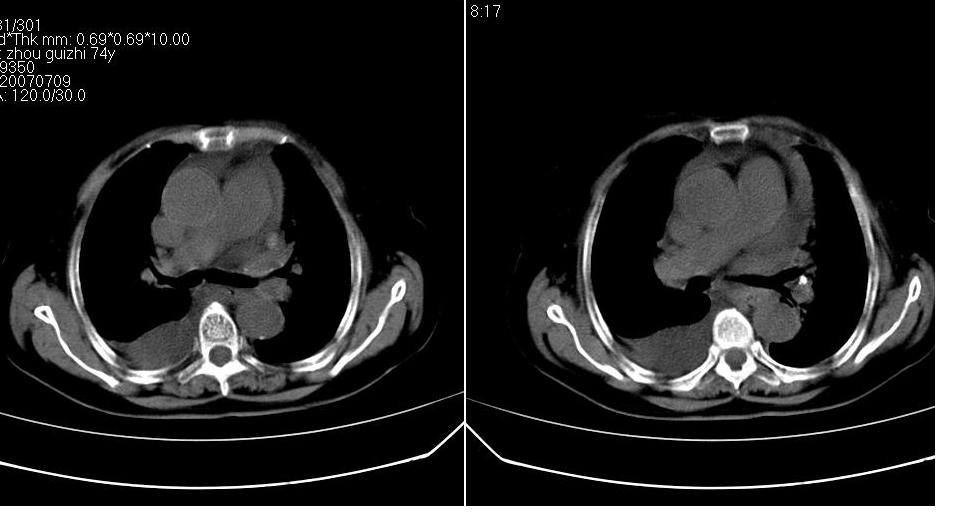

以下是引用zhangzhongshou在2007-7-11 13:16:00的发言:[br]1、冠状动脉钙化[br]2、心包积液[br]3、右侧胸腔积液[br]大家都考虑心衰,冠状动脉钙化、肺纹理增强,胸腔积液、心包积液,表面上是支持,但是为什么右侧有较多积液,左侧没有呢? 如果用结核性胸膜炎,并结核性心包炎也可解释,请楼主进一步提供临床资料。

以下是引用zrs在2007-7-11 14:40:00的发言:[br]支持心衰,心衰所至的胸腔积液常常是右侧多

以下是引用liaizhi在2007-7-11 15:41:00的发言:[br]两肺纹理增粗,肺门影增大,气管支气管通畅。升主动脉壁及冠状动脉壁钙化。左房左室稍扩大。心包积液,胸腔积液。考虑冠心病并心功能不全,肺水肿,胸腔积液。